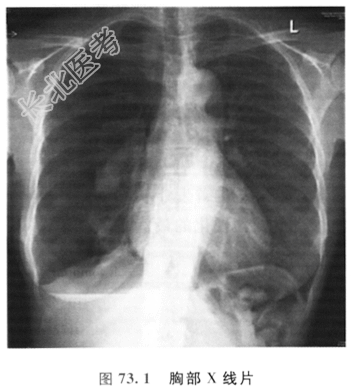

患者女性,25岁,因气短、咳嗽、胸痛6h就诊。6h前患者步行上班时突发胸痛,为右侧胸部锐痛,疼痛随呼吸加重;随后的几个小时内胸痛缓解,但深呼吸时仍有轻度疼痛;疼痛后1~2h患者有轻微气短,目前仅在上楼及快步行走时觉气短,另诉有干咳。4年前发生过类似的情况,但患者不太确定那次胸痛位置是否在左侧。吸烟15支/天,饮酒10个酒精单位/周。偶吸大麻。无其他用药史。职业为会计师。无相关家族史。

脉搏:88/min;呼吸:20/min;血压:128/78mmHg。精神可,无发绀。心音正常。呼吸系统查体:气管和心尖搏动无移位;呼吸动度和叩诊大致正常;右侧触觉语颤减弱,呼吸音降低;右下肋膈角可闻及胸膜摩擦音;听诊未闻及其他附加音。

患者的胸部X线检查结果如图73.1所示

- 简答题1、患者的X线检查结果说明什么问题?